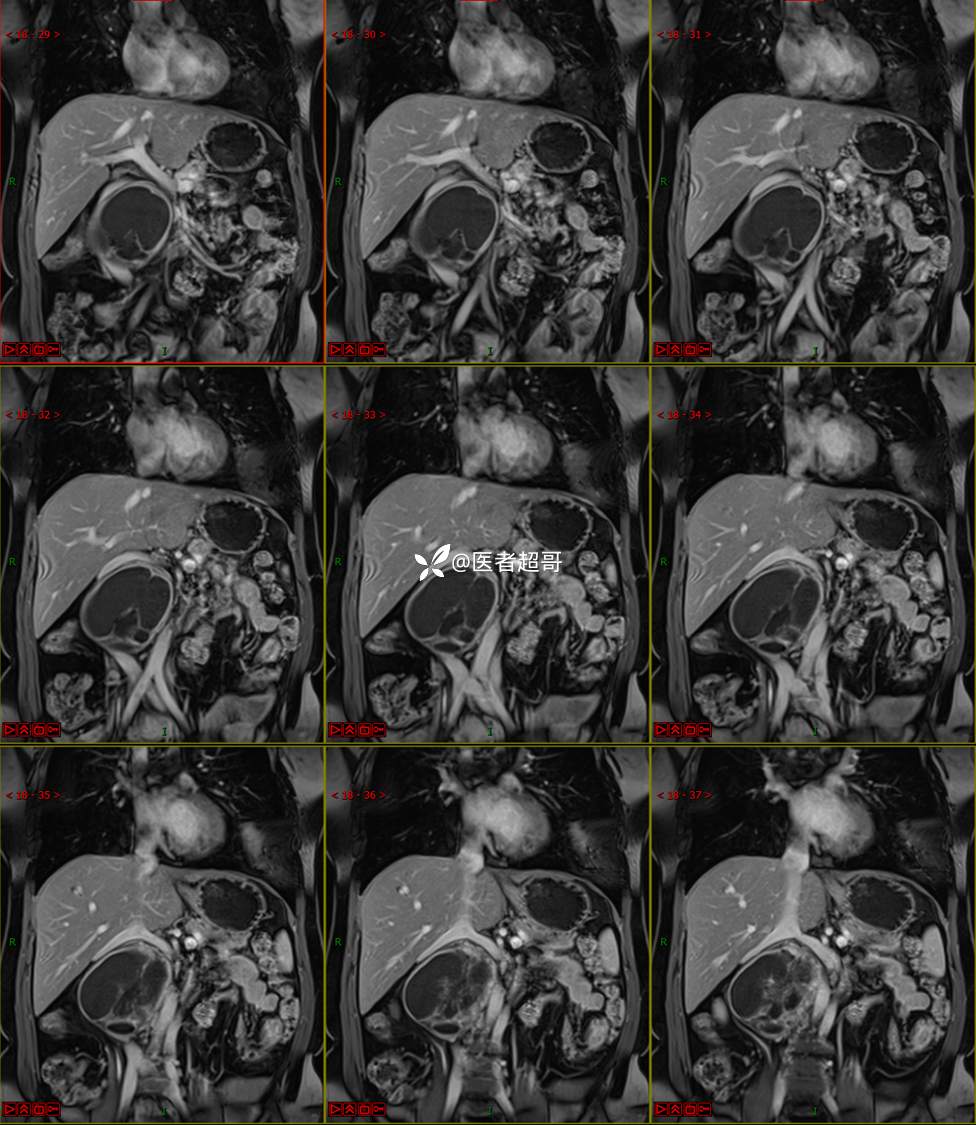

【影诊笔记671】定位有难度,究竟是腹腔内or腹膜后,请先定位,再定性!有结果~~~

专科检查:腹部平坦,腹肌软,无压痛及反跳痛,无包块,肝脾无肿大,Murphy征阴性,腹部叩鼓,肝脾双肾无叩痛,移动性浊音阴性,肠鸣音正常。我院 肝胆胰脾肾彩超提示:脂肪肝、腹腔内囊实性团块,建议进一步检查。